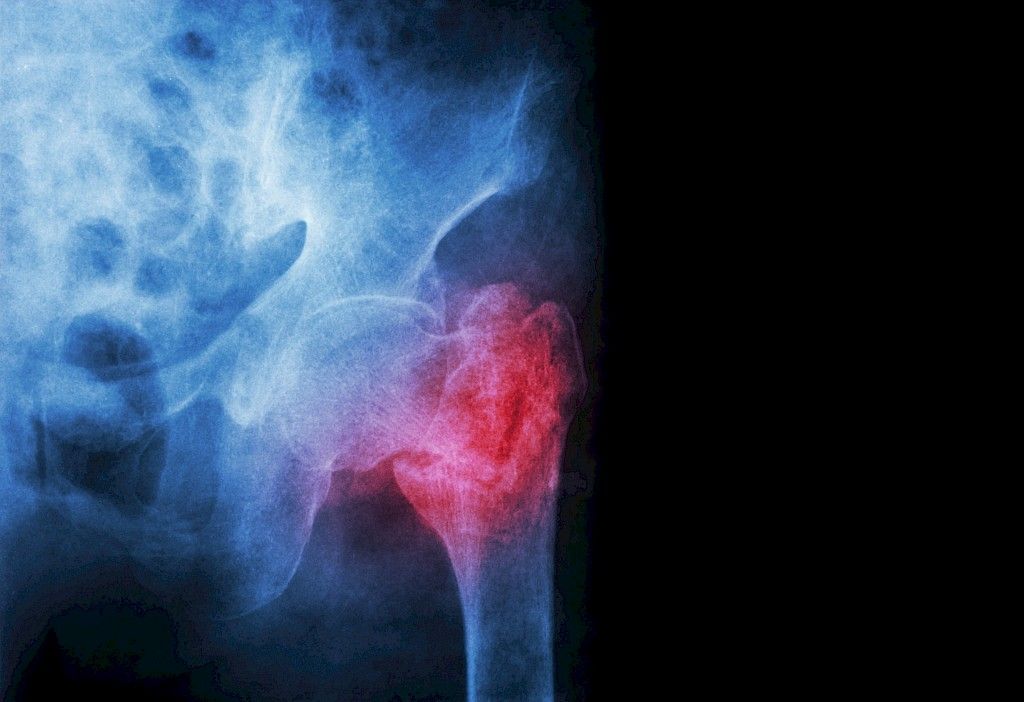

Yli vuorokauden odotusaika lisää lonkkamurtumapotilaiden kuolleisuutta

Suomessa päivystystä ollaan keskittämässä yhä harvempiin sairaaloihin ja välimatkat sekä odotusaika leikkaushoitoon pitenevät. Väestön vanhetessa ja osteoporoosin lisääntyessä lonkkamurtumien määrä kasvaa erityisesti vanhuksilla. Odotusajan pitenemisen voi odottaa lisäävän hoidon komplikaatioita ja kuolleisuutta.

Kanadalaisessa 72 sairaalan murtumapotilaiden aineistossa tutkittiin leikkauksen odotusajan vaikutusta lonkkamurtumapotilaiden kuolleisuuteen. Potilaiden keski-ikä oli 80,1 vuotta ja 70,5 % oli naisia.

Sairaalakuolleisuus (30 vrk) oli koko aineistossa 7,0 %. Kun odotusaika sairaalassa leikkaukseen oli pitempi kuin 24 tuntia, 30 vrk:n kuolleisuus kasvoi 5,8 %:sta 6,5 %:iin. Myös leikkauskomplikaatiot lisääntyivät (esim. pneumoniat, sydäninfarktit, keuhkoemboliat) merkittävästi, kun odotusaika venyi yli 24 tuntiin.

Sairaalan yhtenä laadun mittarina voidaan pitää odotusaikaa päivystysleikkaukseen ja leikkauskuolleisuutta. Lonkkamurtuman leikkaushoidon paras aikaikkuna on siis alle 24 tuntia. Kuinkahan moni suomalainen sairaala pääsee tähän?